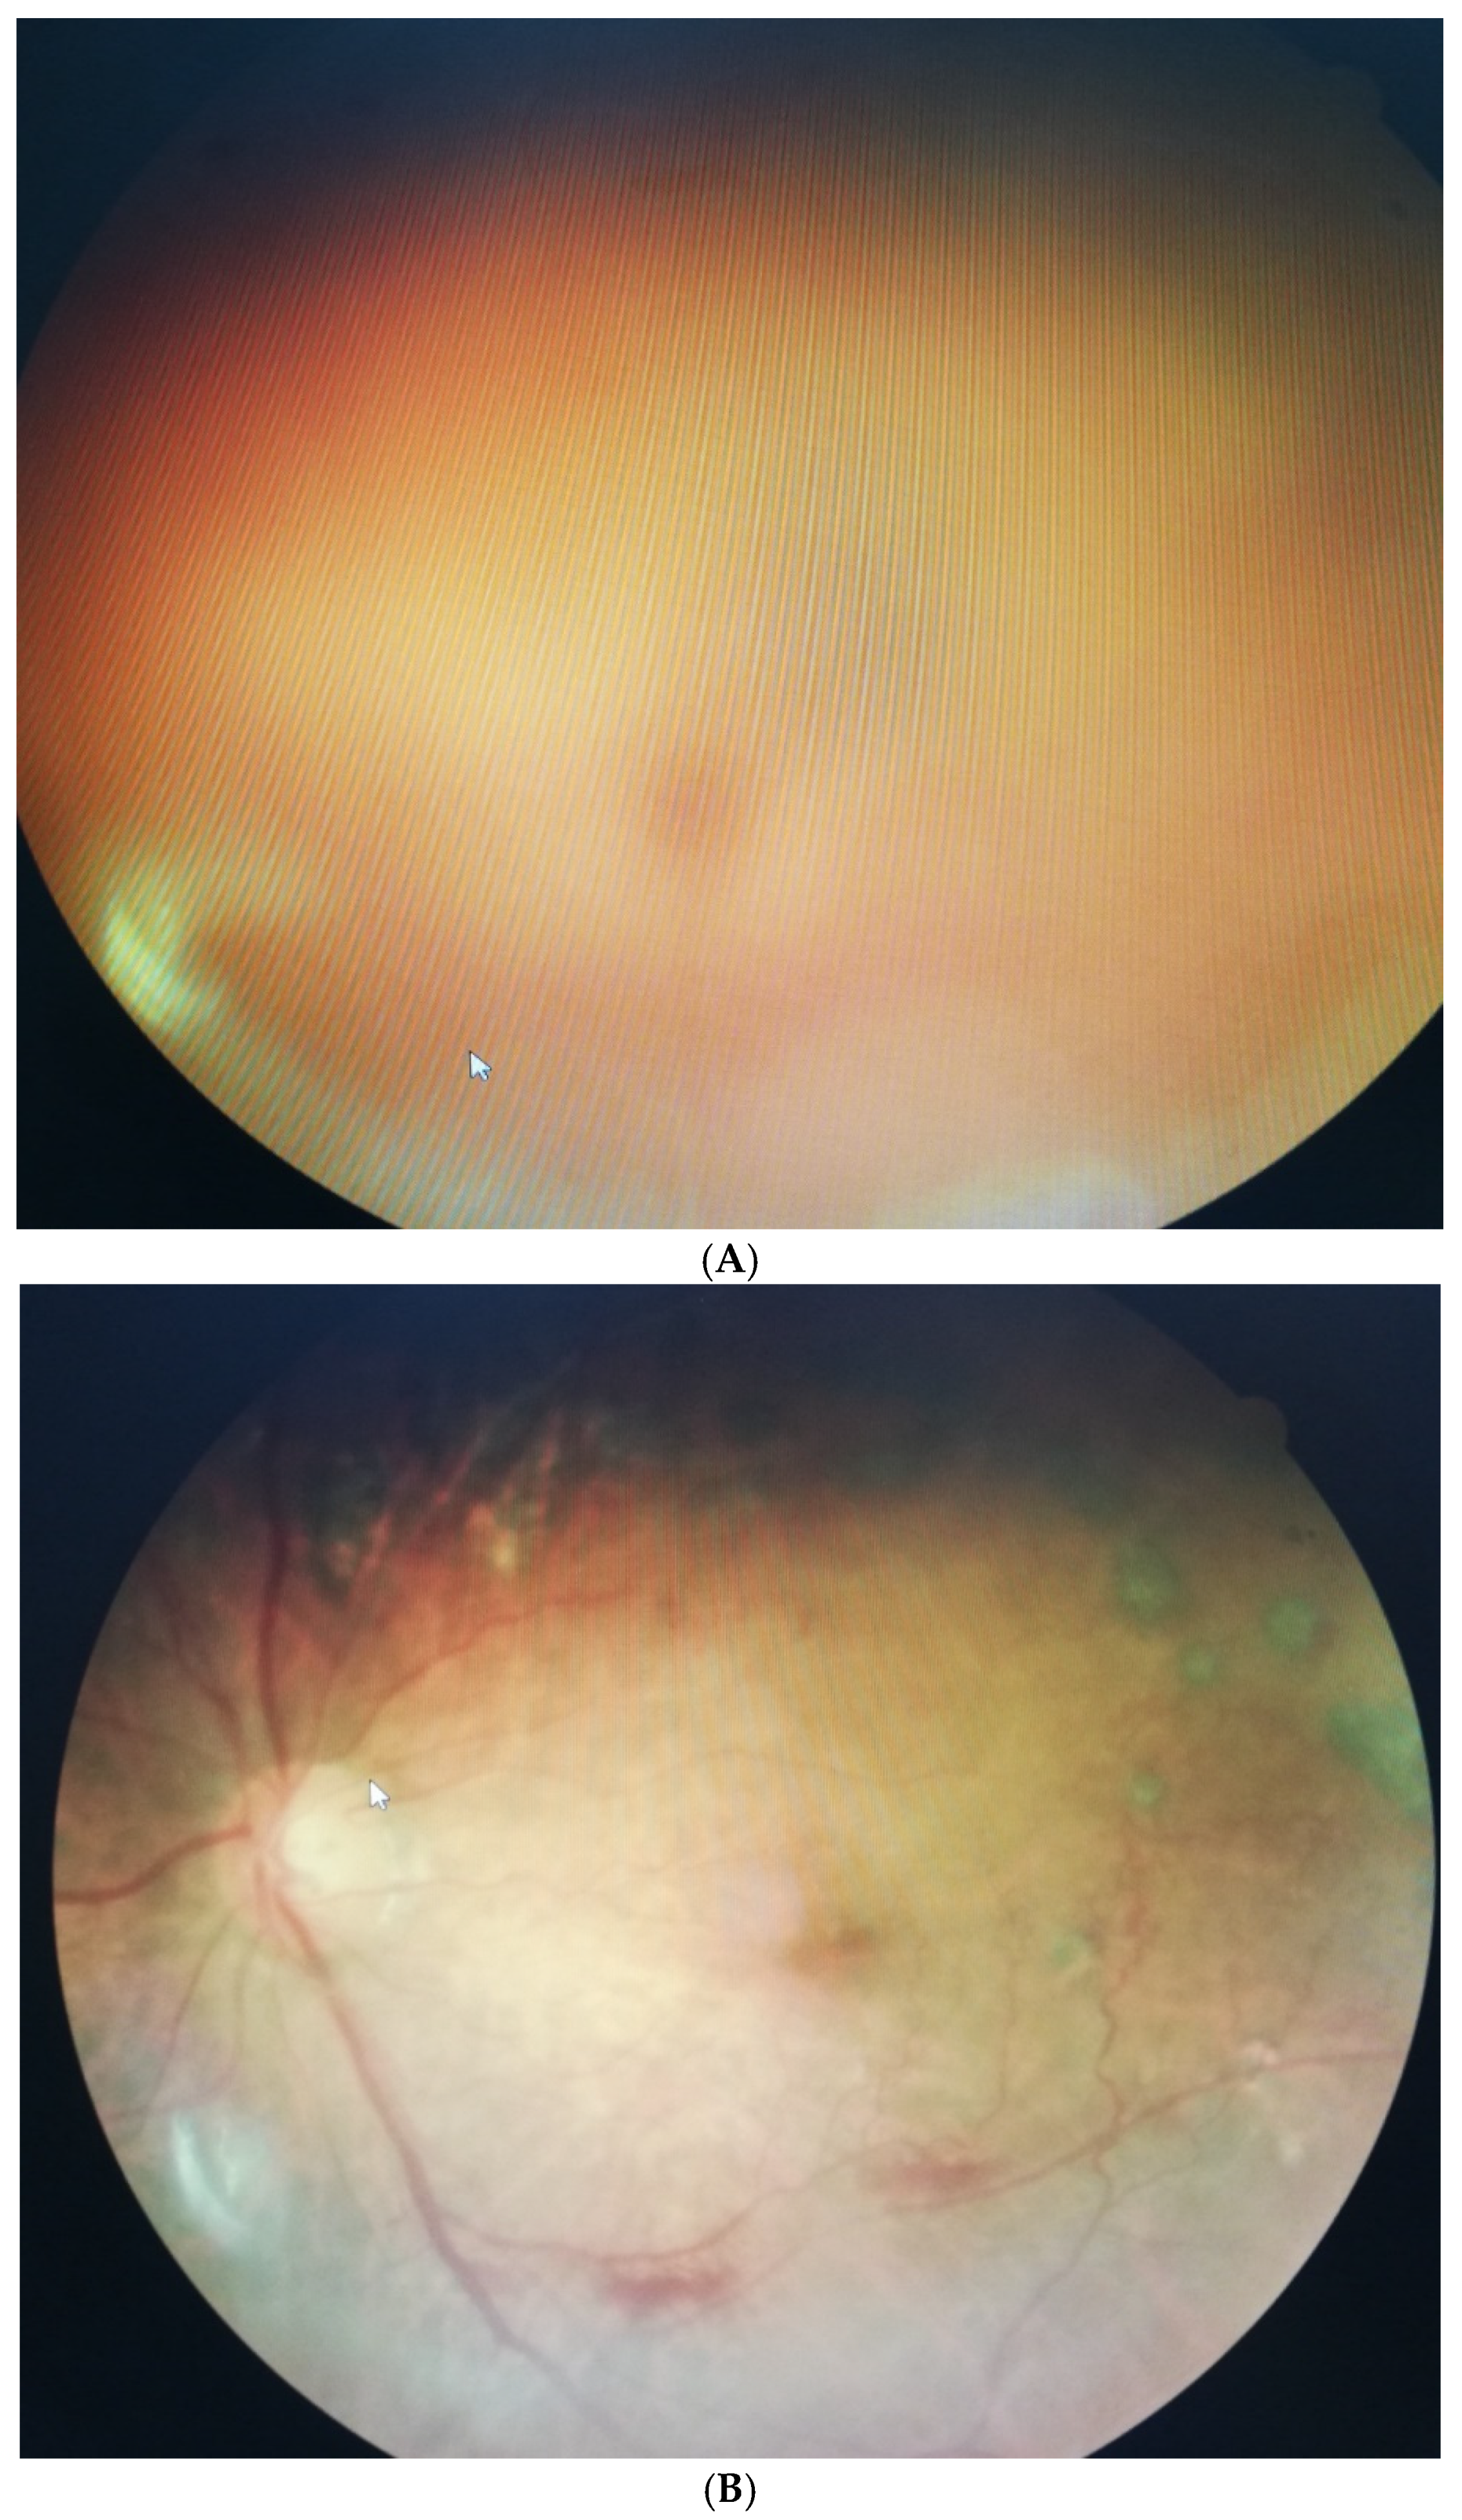

- Takeuichi, M.; Shieh, P.C.; Horng, C.T. Treatment of symptomatic vitreous opacities with pharmacologic vitrelysis using a mixture of bromelain, papain and ficin supplement. Appl. Sci. 2020, 10, 5901. [Google Scholar] [CrossRef]

- Horng, C.T.; Chen, F.A.; Kuo, D.H.; Chen, L.C.; Yen, S.S.; Shieh, P.C. Pharmacologic vitreolysis of vitreous floaters by 3-month pineapple in Taiwan: A pilot Study. J. Am. Sci. 2019, 15, 17–30. [Google Scholar]